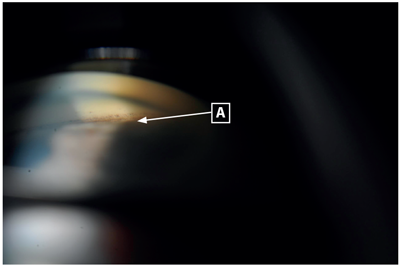

On examination, visual acuity was 6/96 in the right eye and 6/192 in the left eye. Intraocular pressures measured 11mmHg in the right eye and 40mmHg in the left. The left eye was injected, with a mid-dilated, non-reactive pupil and the cornea was cloudy. The anterior chamber appeared shallow in both eyes and there was cataract present in both eyes (nuclear sclerosis) (Figure 1). Gonioscopy revealed no visible angle structures in both eyes (Shaffer grade 0), with the left eye demonstrating extensive peripheral anterior synechiae and the right eye demonstrating appositional closure (Figures 2 and 3). There was no evidence of neovascularisation of the anterior segment.

Figure 1: Slit-lamp anterior chamber photograph of left eye showing deep anterior chamber and nuclear sclerosis.

Figures 2 and 3: Gonioscopy revealed no visible angle structures in both eyes (Shaffer grade 0), the left eye demonstrating extensive peripheral anterior synechiae and the right eye demonstrating appositional closure. A: pigment above Schwalbe’s line from previous appositional closure, now synechial closure in left eye. B: indentation gonioscopy of right eye demonstrating angle opening to reveal trabecular meshwork.